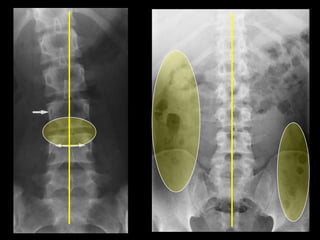

This document provides an overview of normal musculoskeletal imaging. It discusses basic x-ray concepts and densities. It then reviews normal anatomy as seen on x-rays of the skull, spine, pelvis, chest, and extremities. Key anatomical structures are labeled on example x-rays for the shoulder, hip, knee, and foot. Quizzes are included to test recognition of anatomical structures and patient age based on x-rays.